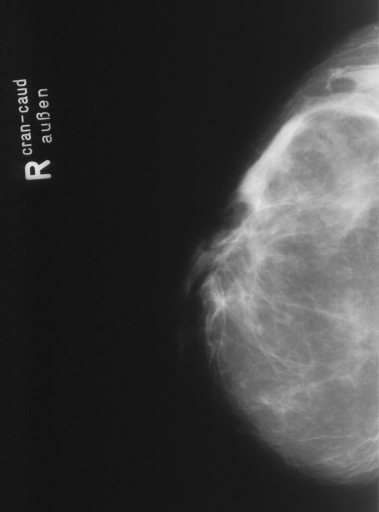

In this series of experiments, we randomly selected three categories from IRMA dataset (namely, breast, foot and lung), and for each category we choose 5 random images from that class (Figures 5, 6 and 7 show these images). When we find “4 out of 180” (4/180) and “8 out of 180” (8/180) projections via micro-DE (tasks that cannot be performed via brute-force), then the question is what can we say about the reconstruction error, in terms of correlation between original and reconstructed images, when we compare evolutionary approximation with the case that we can manage via exhaustive search, namely “4 out of 16” (4/16)? Can micro-DE reach at least the same correlation (similarity) as the brute-force case in lower dimensions? If yes, we may have more confidence in using micro-DE in practice where we cannot apply brute force for benchmarking or direct use, especially for higher dimensions (i.e., the number of projections).

For finding optimal projections based on micro-DE (4 out of 180), we set the parameters of micro-DE to be NFC, , , , and we run each experiment 30 times. For optimal projections based on micro-DE (8 out of 180), we set NFC, , , , and we run each experiment 30 times. The results are presented in Tables 2, 3 and 4. In all cases, micro-DE (MDE) with 4/180 reaches the same correlations as brute force (BF) for 4/16. Of course, MDE finds different projections as it is searching the entire search space of . However, that the same level of reconstruction accuracy can be achieved establishes the reliability of MDE as a practical solution that may even produce a higher-level of uniqueness for Radon barcodes as 4 projections are selected among all 180 angles (the increased uniqueness needs to be verified by applying the Radon barcodes for image retrieval). On the other hand, MDE for 8/180 clearly increases the correlation with statistical significance. This is very encouraging as we can generate more expressive Radon barcodes using a higher number of projections.

| image | BF (4/16) | MDE (4/180) | MDE (8/180) | |||

|---|---|---|---|---|---|---|

| b1 | [22,67,123,157] | 0.83 | [30,50,120,160] | 0.83 | [70,130,30,120,100,150,170,50] | 0.89 |

| b2 | [33,67,123,169] | 0.83 | [30,70,120,160] | 0.83 | [170,140,150,60,40,80,20,110] | 0.89 |

| b3 | [22,67,123,157] | 0.81 | [30,50,120,160] | 0.81 | [150,170,10,70,40,130,110,50] | 0.85 |

| b4 | [11,56,146,169] | 0.81 | [20,60,120,160] | 0.80 | [160,20,120,170,40,30,130,70] | 0.86 |

| b5 | [11,56,112,157] | 0.81 | [20,60,120,160] | 0.81 | [80,20,120,60,160,90,10,140] | 0.86 |